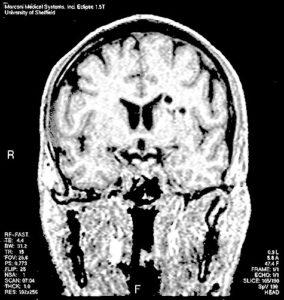

大脑可能是人体中最复杂、最复杂的器官,但它也是最珍贵、最脆弱的器官。大脑受损对有机体来说可能是灾难性的,导致认知障碍,可能导致终生的衰弱症状。林恩·安·巴克(Lynne Ann Barker)和她的同事们正在研究大脑损伤如何导致认知障碍,并开发诊断和治疗创伤性脑损伤的新技术。

她的2006年学习这项研究是第一个通过经验严格的群体研究表明,在头部损伤的情况下脱毛认知受损。她的团体将20名头部伤害和I.Q队列的患者进行了比较。和年龄匹配的控制。两组接受MRI扫描和四个测试的电池,以确定其隐含认知能力。这些测试包括串行反应时间任务(SRT),仅仅是曝光效果任务,自动刻板印象激活和隐藏的协同变化检测。伤害的影响很清楚 - 脑创伤的人在隐性认知的四个测试中的三个中表现较差。有趣的是,SRT任务的性能与执行职能的综合措施相关,这表明这两个方面的认知关系。实际上,作者表明隐式和明确的认知可能相互作用,以产生TBI后观察到的功能障碍行为。而这个领域似乎是注意到这一点 - 在这项工作的出版物之后,已经重新关注了潜意识损害的作用,可以在TBI的行为叛逃中发挥作用。